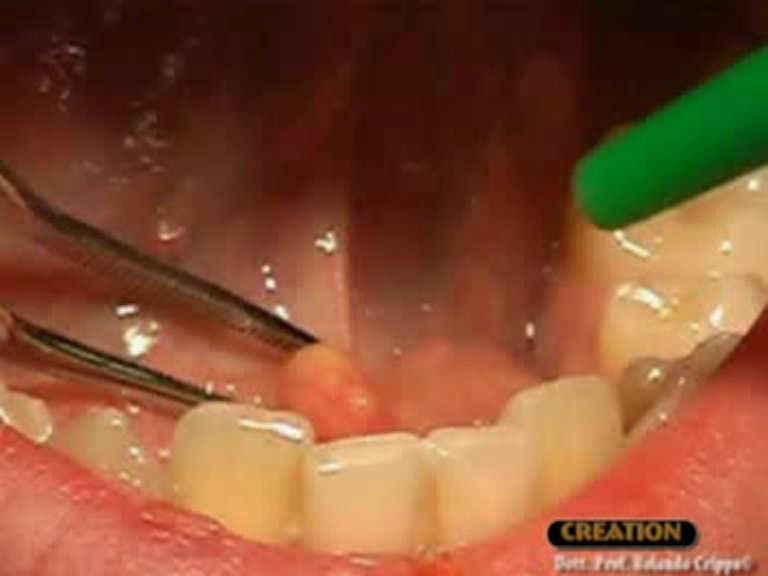

- Some stones may be massaged out by a specialist.

- An ENT or maxillofacial surgeon may canulate the duct to remove the stone (sialotomy).

- A surgeon may make a small incision near the stone to remove it.